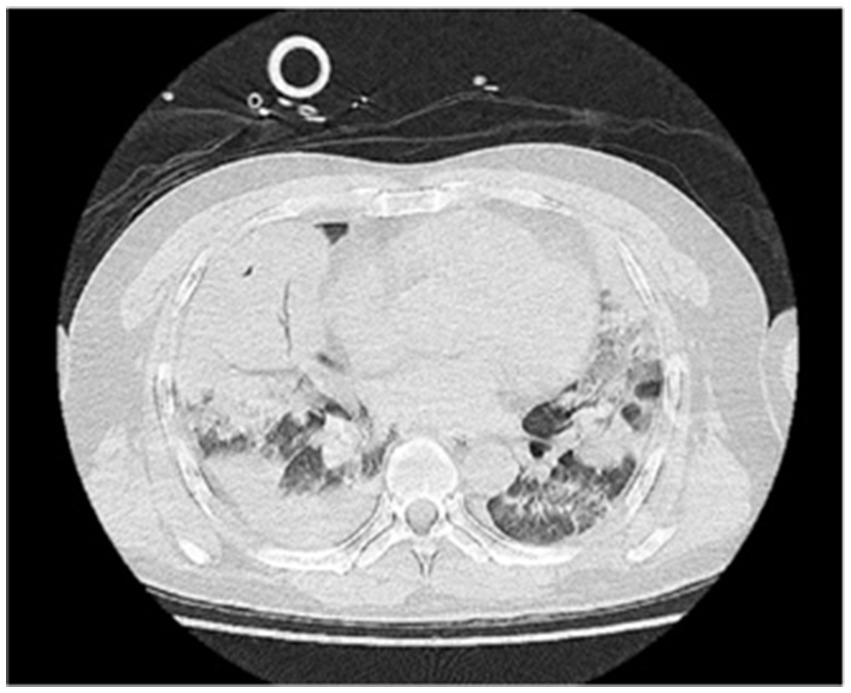

A 48-year-old male was transferred to the emergency department of our hospital from another hospital due to “dyspnea for 4 days after diesel aspiration.” The patient aspirated approximately 50 mL of diesel 4 days ago and immediately developed a choking cough, chest tightness, chest pain, and dyspnea. Emergency chest CT showed extensive exudation and consolidation in both lungs, a small amount of right-sided pleural effusion with adjacent atelectasis of the lung tissue (Figure 1). Fiberoptic bronchoscopy revealed a small amount of yellow - brown thick sputum in the bilateral main bronchi, with mucosal congestion. There was also a small amount of yellow - brown thick sputum in the upper and lower lobes of both lungs, and the airway mucosa of the whole lung was congested, slightly edematous, with scattered bleeding points. The patient’s past medical history included an 8-year history of cerebral infarction and a patent foramen ovale occlusion surgery performed 8 years prior. The comprehensive diagnosis was “aspiration pneumonia (diesel).” Auxiliary examinations indicated ventilation dysfunction (SpO₂: 93%, PaO₂: 68.9 mmHg). The patient was intubated and connected to a ventilator for assisted ventilation and was admitted to the EICU for further treatment.

Figure 1

Figure 1. Lung CT scan upon admission.